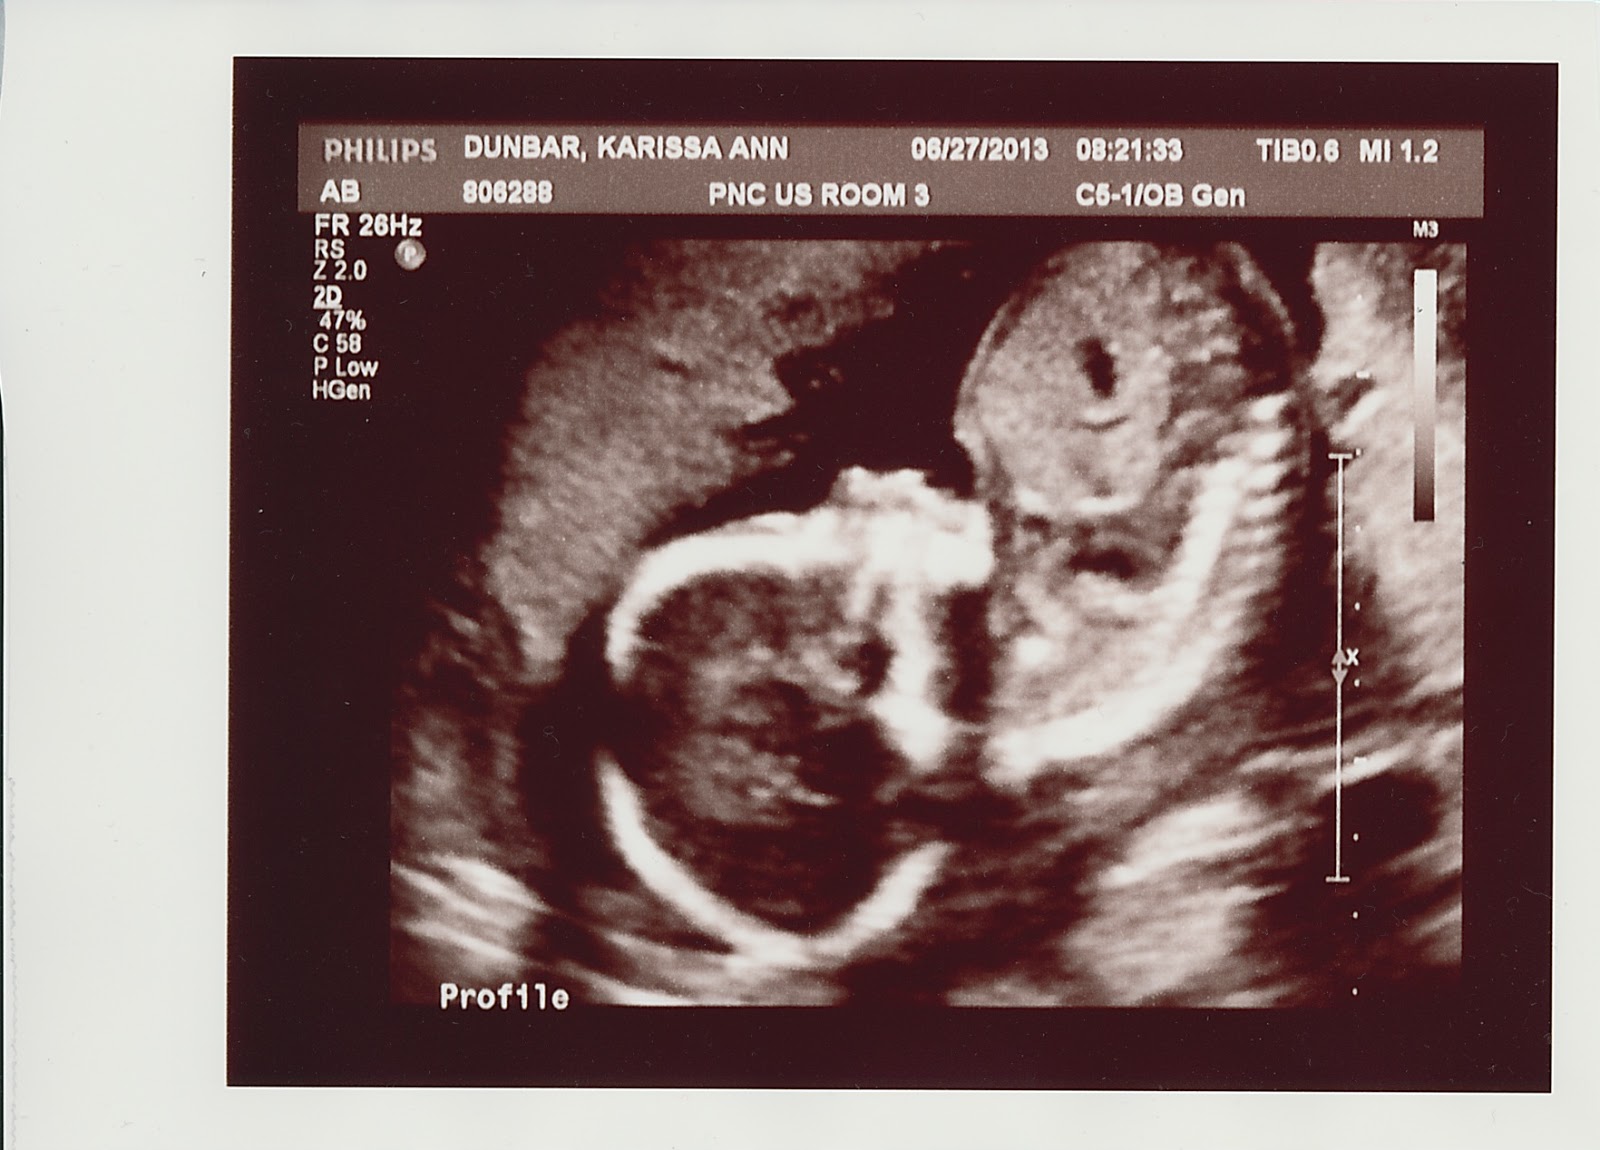

Oh yeah, it’s a girl!  Exciting, right?  I totally cried when the ultrasound technician told us.  Sadly, this does mean MLM (Michael Lary Marshall) is out in terms of names.  I haven’t yet come up with one as totally awesome for a girl.  We’re working on it.  🙂  Check out the ultrasound photos!

So the ultrasound-ologist also got some awesomely creepy baby photos… check these two out: